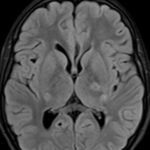

There is a growing body of literature and scientific discovery on pediatric autoimmune encephalitides. This is a heterogenous group of neuroinflammatory conditions leading to often perplexing acute and progressive neurologic and/or neuropsychiatric symptoms. This report demonstrates the evaluation and management of an adolescent with myelin-oligodendrocyte glycoprotein (MOG) antibody-associated fulminant acute disseminated encephalomyelitis (ADEM) in the context of current literature. The featured magnetic resonance imaging uniquely highlights progressive central nervous system lesions detected over the course of the first week of disease.